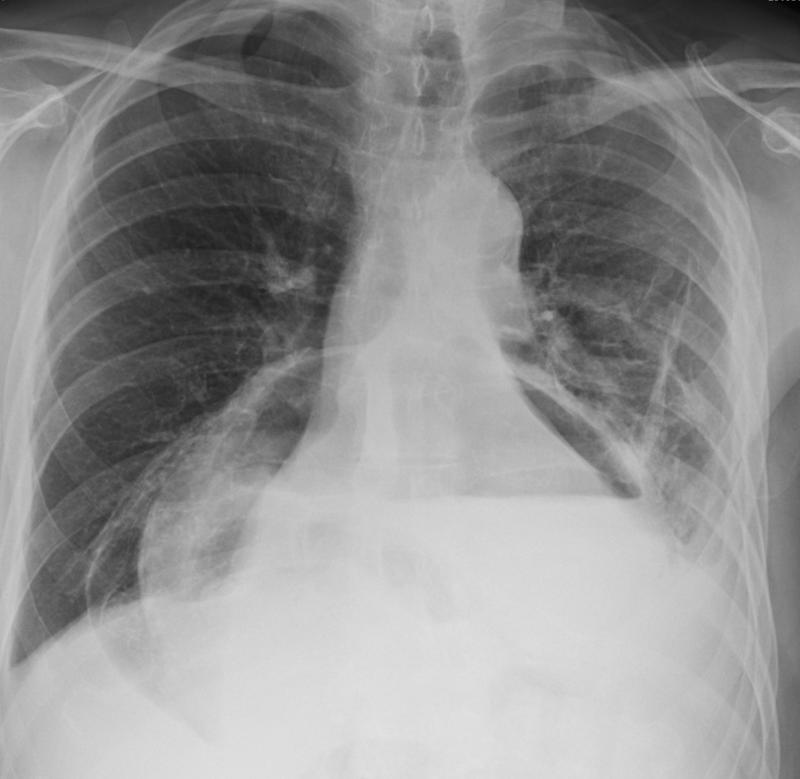

Gallery Mediastinum Hiatus Hernia Hiatus hernia containing stomach and transv colon

Hiatus hernia containing

stomach and transv colon